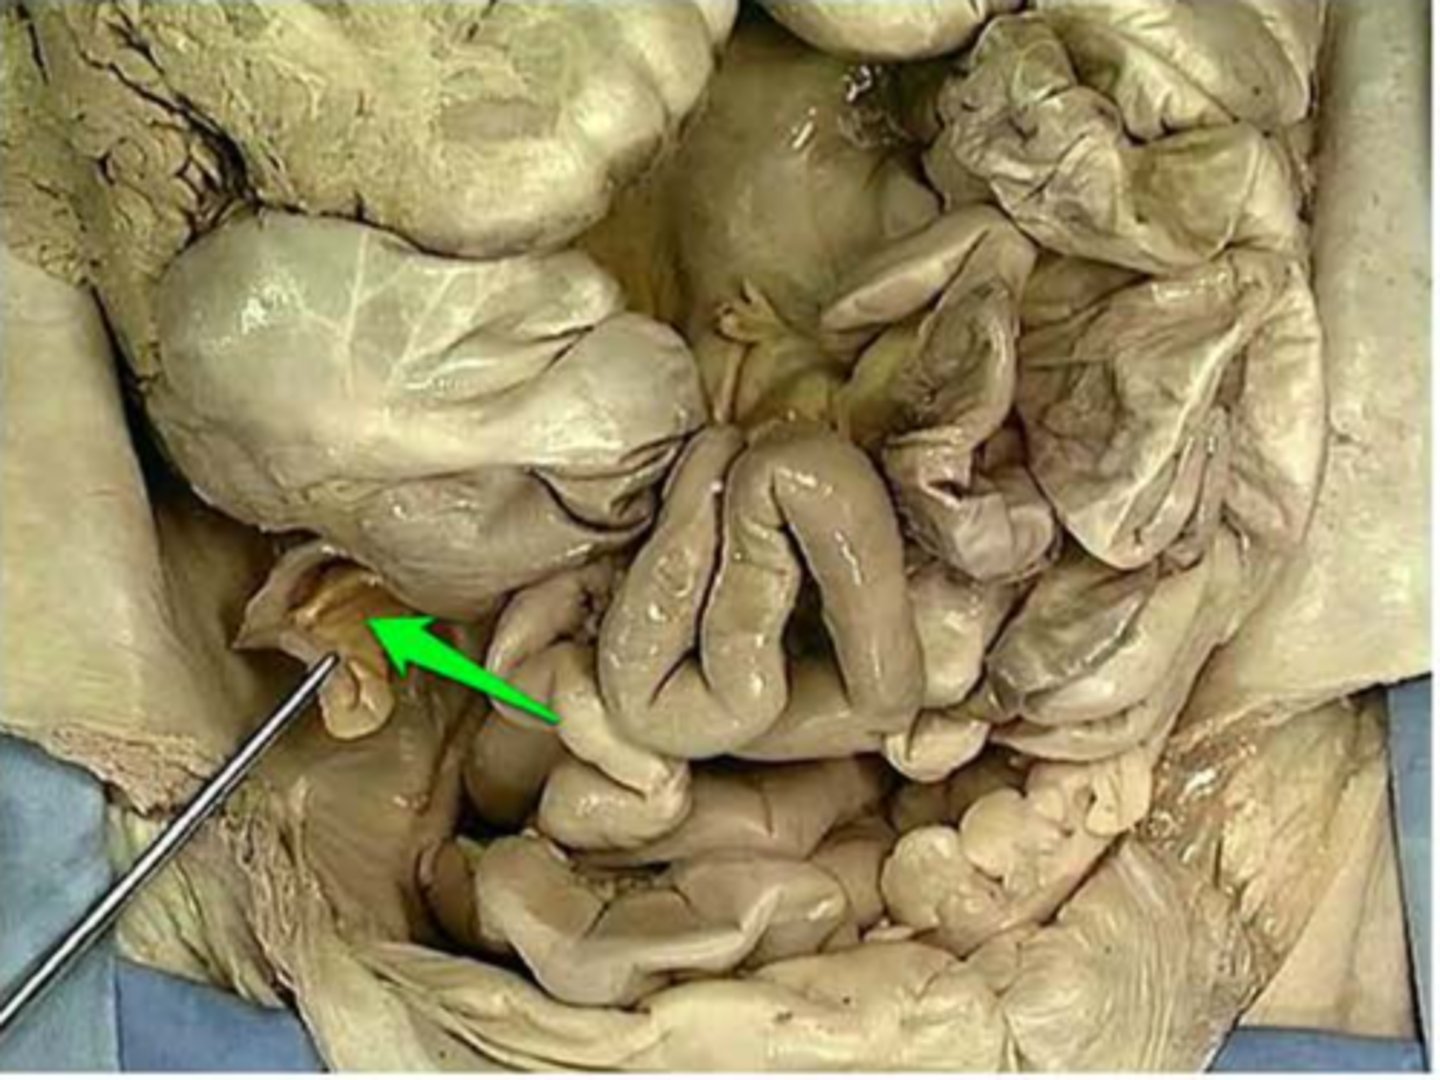

mesoappendix